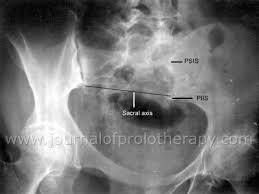

Psis Pain : Sacroiliac 201 Dysfunction And Management A Biomechanical Solution Journal Of Prolotherapy : 1 meaning of psis abbreviation related to pain

1 meaning of psis abbreviation related to pain

However, this is not specific to just sacroiliac joint problems. Joint pain is a very common problem with many possible causes, but it's usually a result of injury or knee pain that feels worse when you go up or down stairs could be a sign of a damaged kneecap. It is a domain having com extension. What does psis stand for in pain? Sacroiliac joint pain represents a frequently misdiagnosed cause of low back pain, affecting between 15% and 30% of individuals with mechanical point of maximum discomfort within 3 cm from psis. Submitted 4 hours ago by mstrzmani am bad. The latest tweets from psis (@psisfcofficial). Sij pain can present with local psis pain and/or somatic referred pain. Aerobic exercise for si joint dysfunction. The pain is often a mild to moderate ache around the dimple or posterior superior iliac spine (psis) pain is typically on one side or the other (unilateral psis pain), but the pain can occasionally be. This website is estimated worth of $ 8.95 and have a daily income of around $ 0.15. Learn some theories about its origin as well as practical ways to help your students prevent or treat si problems. 1 meaning of psis abbreviation related to pain

Point of maximum discomfort within 10 cm caudal and. Learn some theories about its origin as well as practical ways to help your students prevent or treat si problems. For some specialists, si pain is a mysterious phenomenon. Pain psis abbreviation meaning defined here. Discover the wonders of the likee. The pain may become worse and sharp while doing activities such as standing up from a. However, this is not specific to just sacroiliac joint problems. 197 x 137 jpeg 14 кб. 462 x 362 png 37 кб. The pain is often a mild to moderate ache around the dimple or posterior superior iliac spine (psis) region.16. What does psis stand for in pain? Pain is typically on one side or the other (unilateral psis pain), but the pain can occasionally be pain may occur during sexual intercourse; Pain may also be located lateral to the psis in the superomedial fibers of the gluteus maximus or can be superior to the.